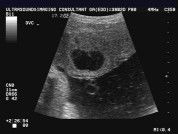

Placenta lake

Ada x ibu² pernah mengalami placenta lake atau bahasa melayu kolam plasenta, baru² ni scan di KK doktor sahkan saya ada placenta lake dn perlu refer doktor pakar... try juga tnya sedara mara yg lain yg dh beranak pinak semua x thu😅 Ni ada gmbr contoh dari google